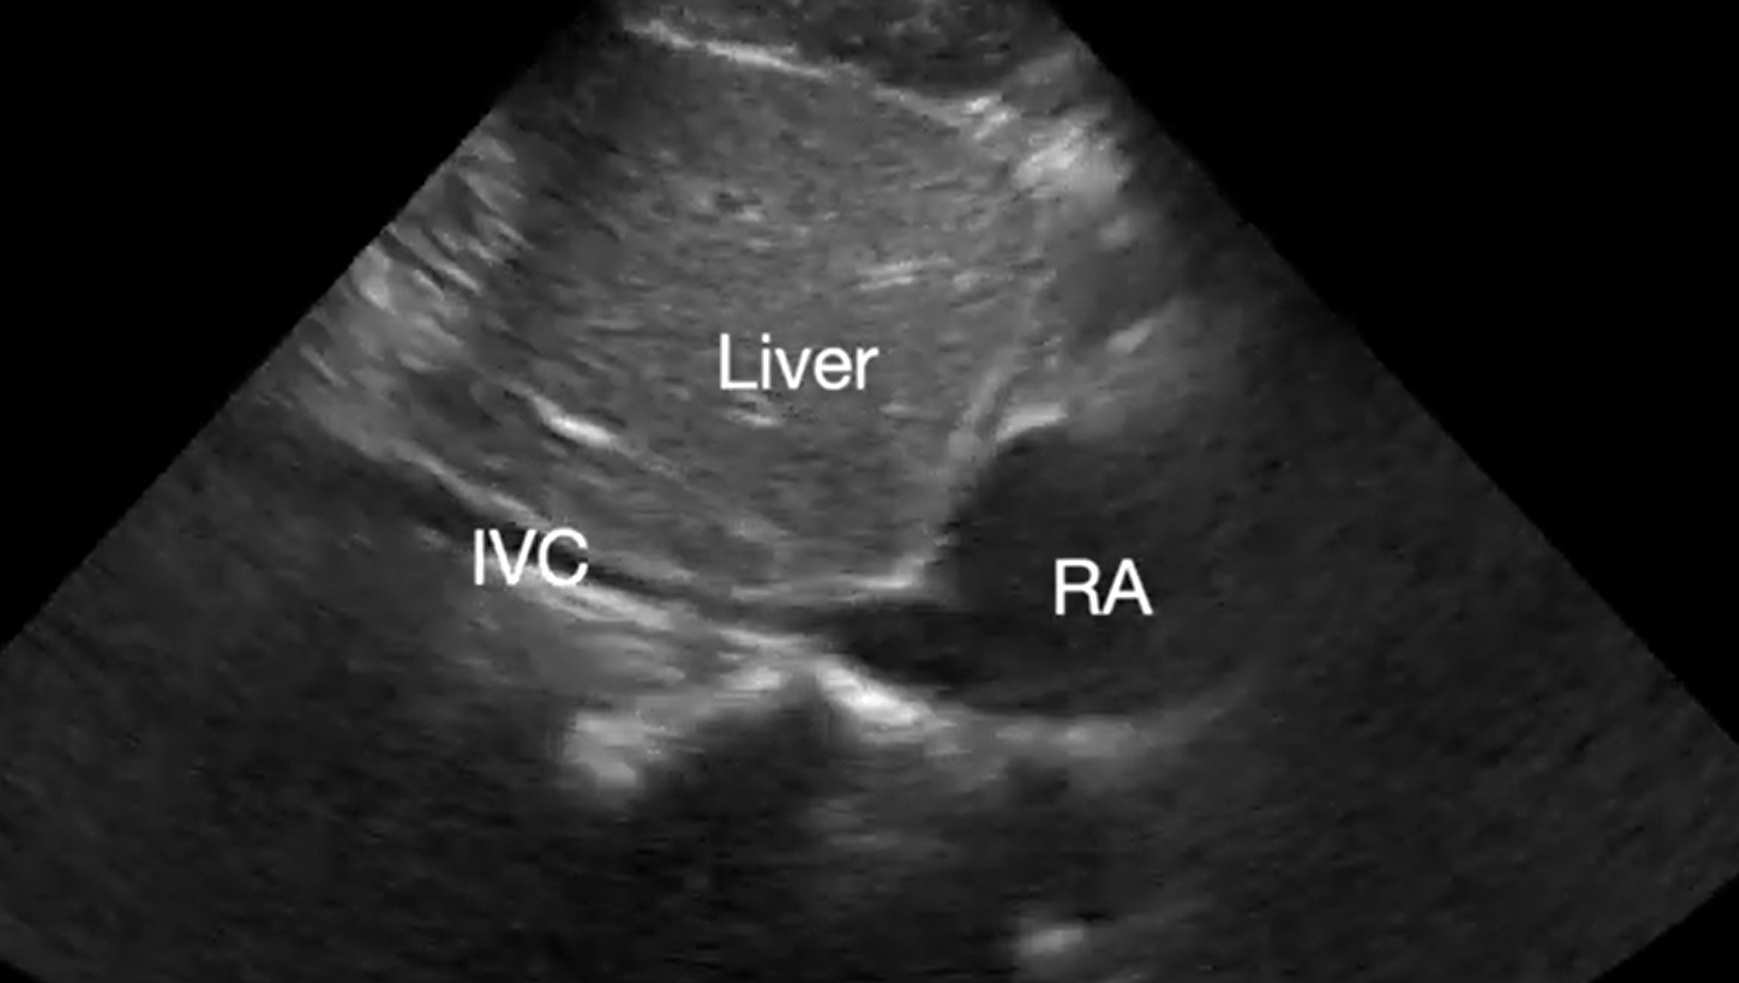

Pericardial tamponade is identified in 5%-22% of patient with PEA arrest.6,7 POCUS findings of pericardial tamponade include the presence of either small (acutely developing) or large (chronically developing) pericardial effusion, right atrial (RA) systolic collapse, right ventricular (RV) diastolic collapse, and plethoric inferior vena cava (IVC) (Videos 2 and 3). The diagnosis of tamponade using POCUS may be difficult in post-cardiac surgery patients who frequently present with a localized collection; transesophageal echocardiography (TEE) should then be used to make the diagnosis. A concomitant pleural effusion might potentially worsen the tamponade physiology. Therefore, imaging of the pleural space can be performed during chest compressions, with thoracentesis possibly reversing the tamponade physiology8 (Video 4).

Supplemental Video 3. Subcostal IVC view demonstrating plethoric inferior vena cava (IVC) during chest compressions. RA, right atrium. (click to view)